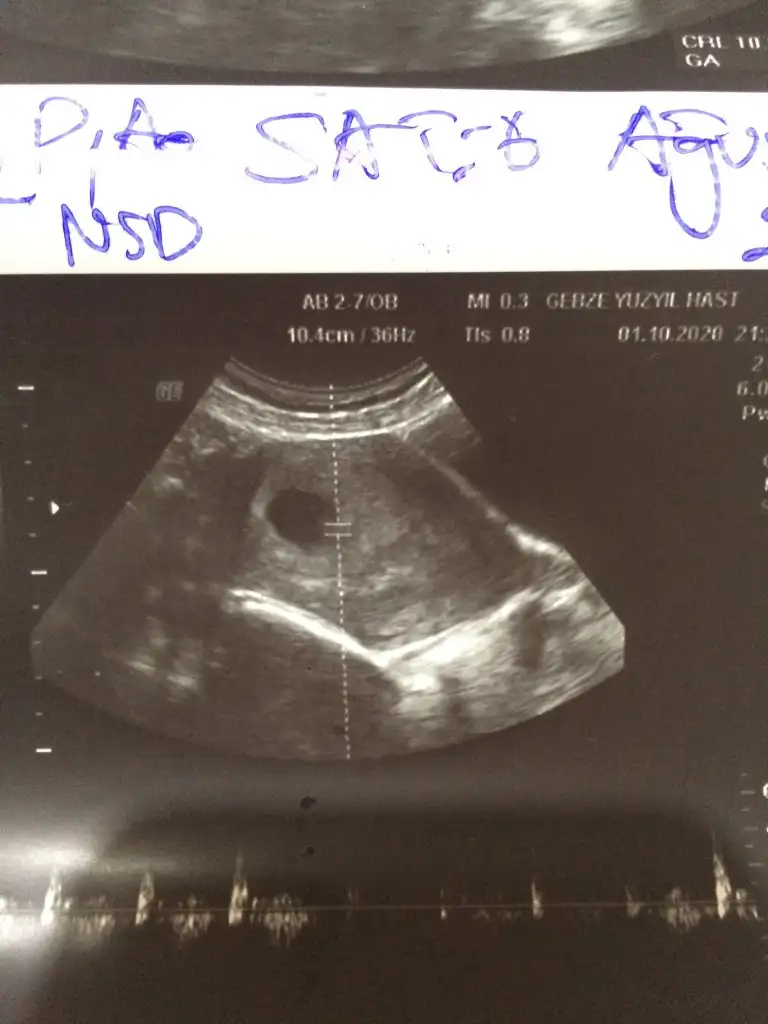

Bana da yorum yapar misiniz biraz kucuk ama 😊 6+4 deki ultrason goruntumuz, kalp atisi 150'ydi 😊

6-7 haftalık gebelikte bebek plasentaya çok yakın konumdadır ve elinizdeki vajinal görüntüde bebek sağdaysa erkek. Bu yöntem %97 doğrudur yazıyor sitede